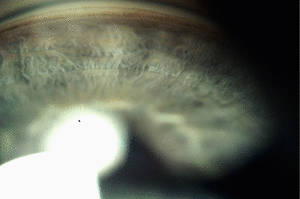

الشبكة الحويجزية/التربيقية (Trabecular Meshwork) هي منطقة من الأنسجة في العين تقع حول قاعدة القرنية ، بالقرب من الجسم الهدبي ، وهي مسؤولة عن تصريف الخلط المائي من العين عبر الغرفة الأمامية (الغرفة الموجودة في مقدمة العين المغطاة القرنية).

النسيج إسفنجي ومبطن بالخلايا الترابيقية. يسمح للسائل بالتدفق إلى مجموعة من الأنابيب تسمى قناة شليم والتي تصطف بواسطة البطانة مع خصائص الدم واللمفاوية التي تسمح للخلط المائي بالتدفق إلى نظام الدم..[1]

الزرق

يُعتقد أن معظم حالات الزرق (وإن لم تكن كلها) ناتجة عن زيادة ضغط العين. يزداد الضغط إما عند إنتاج الكثير من سائل الخلط المائي أو عن طريق انخفاض تدفق الخلط المائي. الشبكة التربيقية هي المسؤولة عن معظم تدفق الخلط المائي. عندما يتم حظر التدفق الخارج ، قد تكون هناك حاجة إلى تدخلات مثل استئصال التربيق أو رأب التربيق أو التحويلة المائية لاستعادتها.